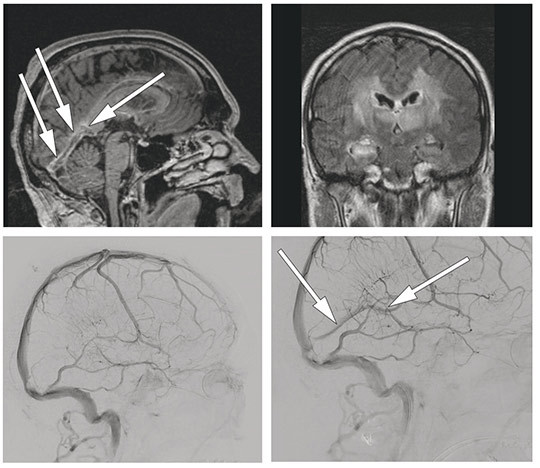

På cerebral kontrastforsterket og T1-vektet MR-bilde (øverst til venstre) vises kontrastutsparing i midtlinjen i v. cerebri magna (v. Galeni) og sinus rectus (piler). Øverst til høyre ses bilaterale signalforandringer på FLAIR, som følge av cerebral venetrombose.

Det ble utført endovaskulær behandling på vital indikasjon. Man fikk tilgang til det intrakraniale venesystem via et kateter fra høyre v. femoralis til høyre v. jugularis interna. Et mikrokateter ble ført gjennom sinus transversus og sigmoideus til sinus rectus og v. Galeni. Etter trombeaspirasjon og trombektomi med Solitaire temporær stent var sinus rectus og v. Galeni rekanalisert. Nederst til venstre vises cerebral angiografi i venefase (sidebilde) etter kontrastinjeksjon i venstre a. carotis interna før trombektomien og nederst til høyre etterpå. Pilene markerer åpne ovennevnte venestrukturer etter behandling.